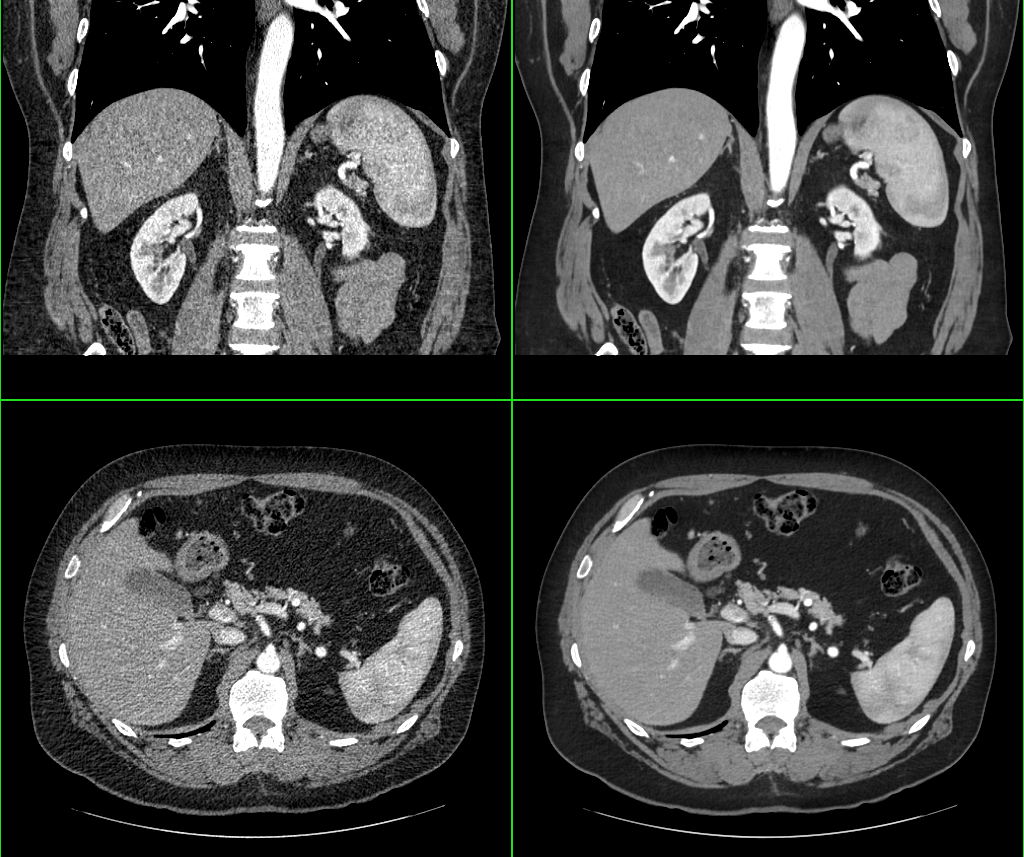

La squadra del Dott. Caruso e del Prof. Laghi è stata tra i primi in Italia ad utilizzare l’algoritmo di intelligenza artificiale (AI) in Tomografia…